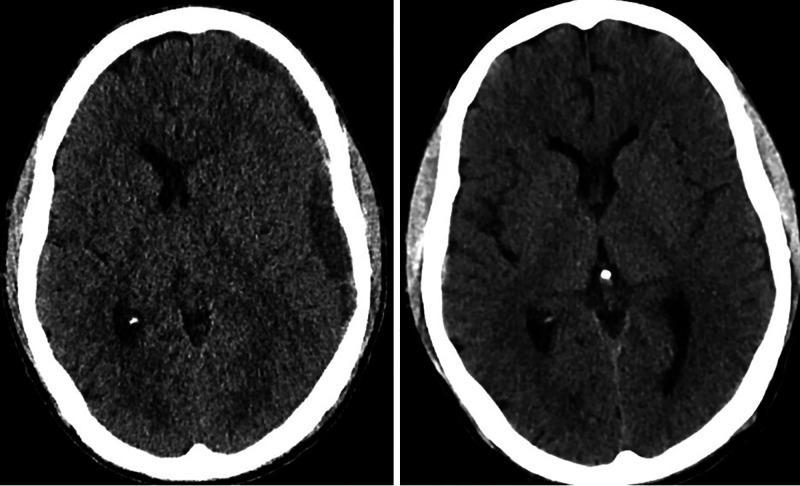

A 35-year-old man who had severe thrombocytopenia due to blast cell crisis with chronic myeloid leukemia developed an atraumatic CSDH. The patient developed severe headaches in the hospital while being treated for febrile neutropenia. He remained neurologically intact. MMA embolization was undertaken due to the morbidity and mortality risks associated with surgery and the high risk of recurrence due to severe thrombocytopenia. At 2 months post-procedure the patient was asymptomatic and there was almost complete resolution of the hematoma.

一名35岁男性因慢性粒细胞白血病原始细胞危象导致严重血小板减少症,进而发生了非创伤性CSDH。该患者在因发热性中性粒细胞减少症接受治疗期间在医院出现严重头痛。其神经系统保持完好。由于手术相关的发病和死亡风险以及严重血小板减少症导致的高复发风险,遂进行了MMA栓塞术。术后2个月,患者无症状,血肿几乎完全消退。